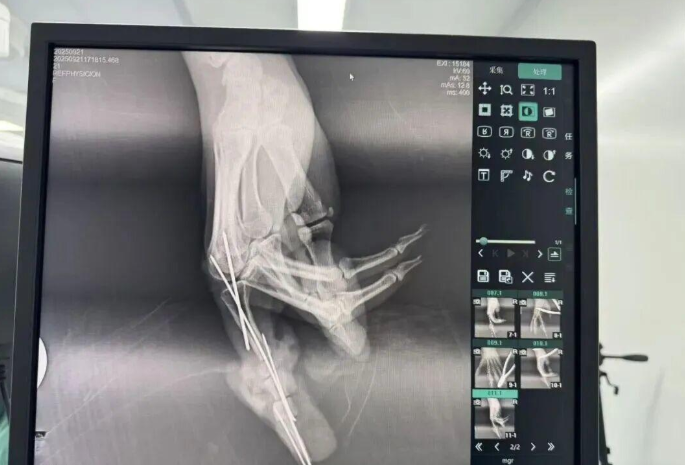

为确保手术成功,杨志主任特别联合刘金海主任组成多手术组协作团队,充分发挥梯队配合优势,反复研讨后确定了“组合式”手指再造方案:利用右足踇趾的皮瓣、末节甲床及部分趾骨,联合第二趾的趾间关节,再取部分髂骨进行精确植骨,将这些组织精密拼装,重建一个兼具良好外形和功能的新示指。

手术当天,多手术组梯队配合的优势得到充分体现。无影灯下,杨志主任与团队各司其职、紧密配合,一场漫长的生命接力就此展开。在放大40倍的专业手术显微镜下,医生们开始了精细操作。杨志主任在术后解释道:“患者需要吻合的血管直径仅0.5-1.0毫米左右,末节手指的毛细血管更是细如发丝。我们必须将移植组织与手部的血管、神经、肌腱进行精准吻合,确保移植组织通血成活。这不仅要求医生有扎实的显微外科技术,还要具备专业的整形外科审美能力,才能让再造的指尖既好用又好看。”

技术亮点,在时间淬炼下的毫米级艺术